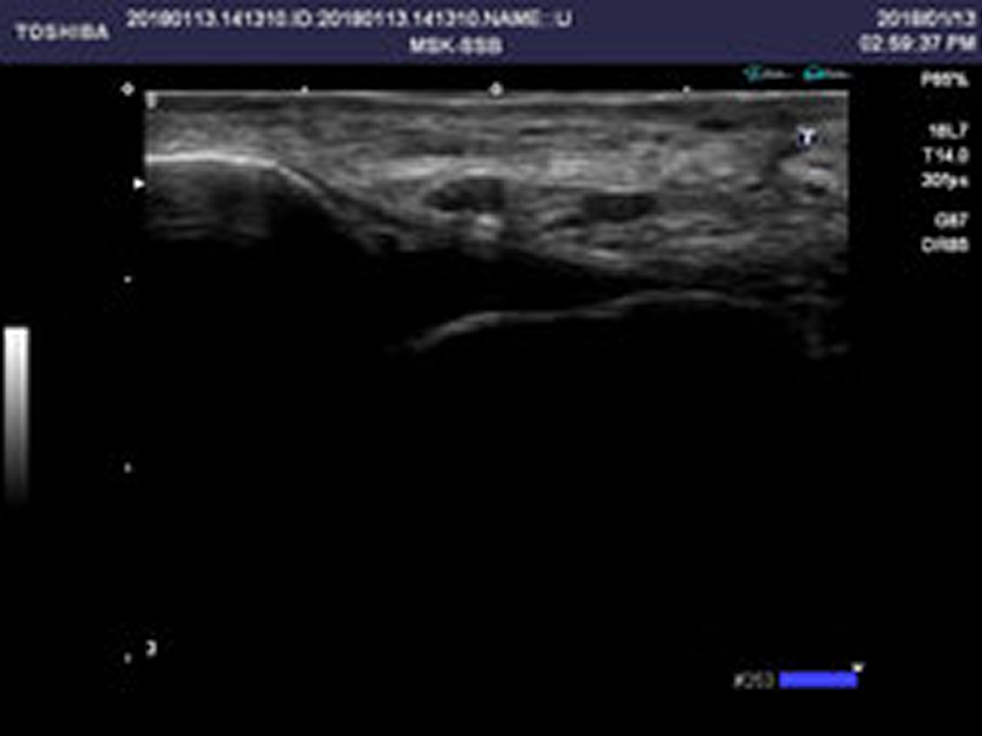

超音波画像診断装置

当院では、超音波による画像検査を行っています。捻挫や打撲、骨折などの判断だけではなく、痛みの原因特定を行うことで、より的確な施術が可能です。